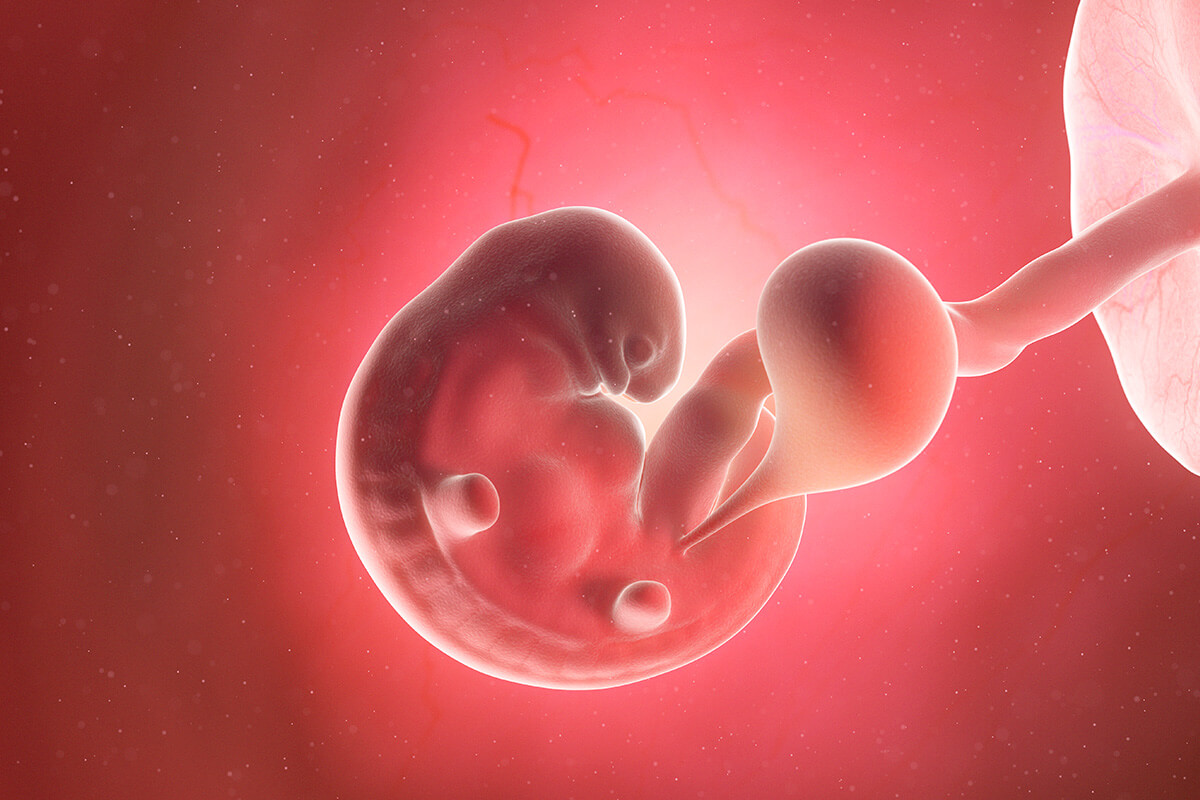

En la semana 6, tu bebé ya mide de 2 a 5 milímetros; casi el mismo tamaño de una lenteja. Sus extremidades comienzan a alargarse, así que ya no son incipientes al costado del tronco, como en la semana 5, sino que toman forma de brazos y piernas; incluso, ya podrán diferenciarse los pies y las manos.

Su pequeño corazoncito late con la fuerza suficiente para ser observable con un ecosonograma intravaginal, así que si te realizas este examen durante esta semana podrás escuchar los latidos del corazón de tu bebé. Este será un momento que quedará guardado para siempre.

El cerebro continúa desarrollándose, mientras que inicia la formación de los pulmones y una serie de músculos y huesos, al igual que las vesículas ópticas, las que se convertirán más adelante en sus ojos. Del mismo modo sucede con los conductos de sus oídos internos.

Este será el aspecto que tendrá tu bebé en una ecografía durante las semanas 6 y 7 del embarazo: